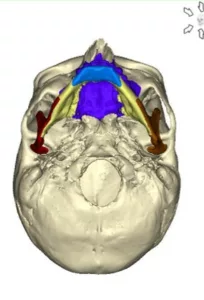

Des miniplaques en titane sur mesure spécifiques de l’anatomie propre à chaque patient et spécifiques des mouvements envisagés par le chirurgien permettent de stabiliser toutes les pièces anatomiques libérées par les manœuvres d’ostéotomie conformément à la simulation : plateau maxillaire, arc denté mandibulaire, branches montantes et condyles, menton .

Ostéotomie de Lefort I en 1, 2 ou 3 fragments, ostéotomie sagittale des branches montantes, génioplasties, ostéotomies segmentaires maxillaires et mandibulaires, postérieures ou antérieures, plus rarement ostéotomies de Lefort II ou Lefort III, tous les types d’ostéotomies peuvent être réalisés en chirurgie guidée.